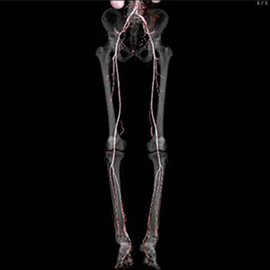

閉塞性動脈硬化症(ASO)に対する下肢CTangio、肺梗塞・深部静脈血栓症の精査、外傷全身CT、狭心症疑いに対する心臓CT、外科術前精査など各科からの依頼に迅速に対応しております。

また、CTの更新に伴い3次元画像解析ワークステーションsynapseVINCENTを最新版にバージョンアップしました。 FUJIFILM独自のAI技術を搭載し、自動抽出機能が充実したことで、整形領域をはじめ、冠動脈解析、肝切除術前シミュレーション、大腸癌術前CTcolonographyにおいて、より短時間で高精度な3D解析ができるようになりました。

CTの検査画像例